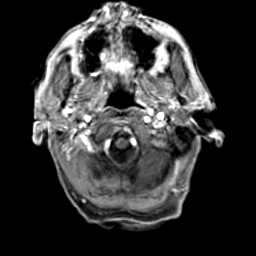

Glioma Overlay -- Slice #1

[Home][Help][Clinical] Slice 1